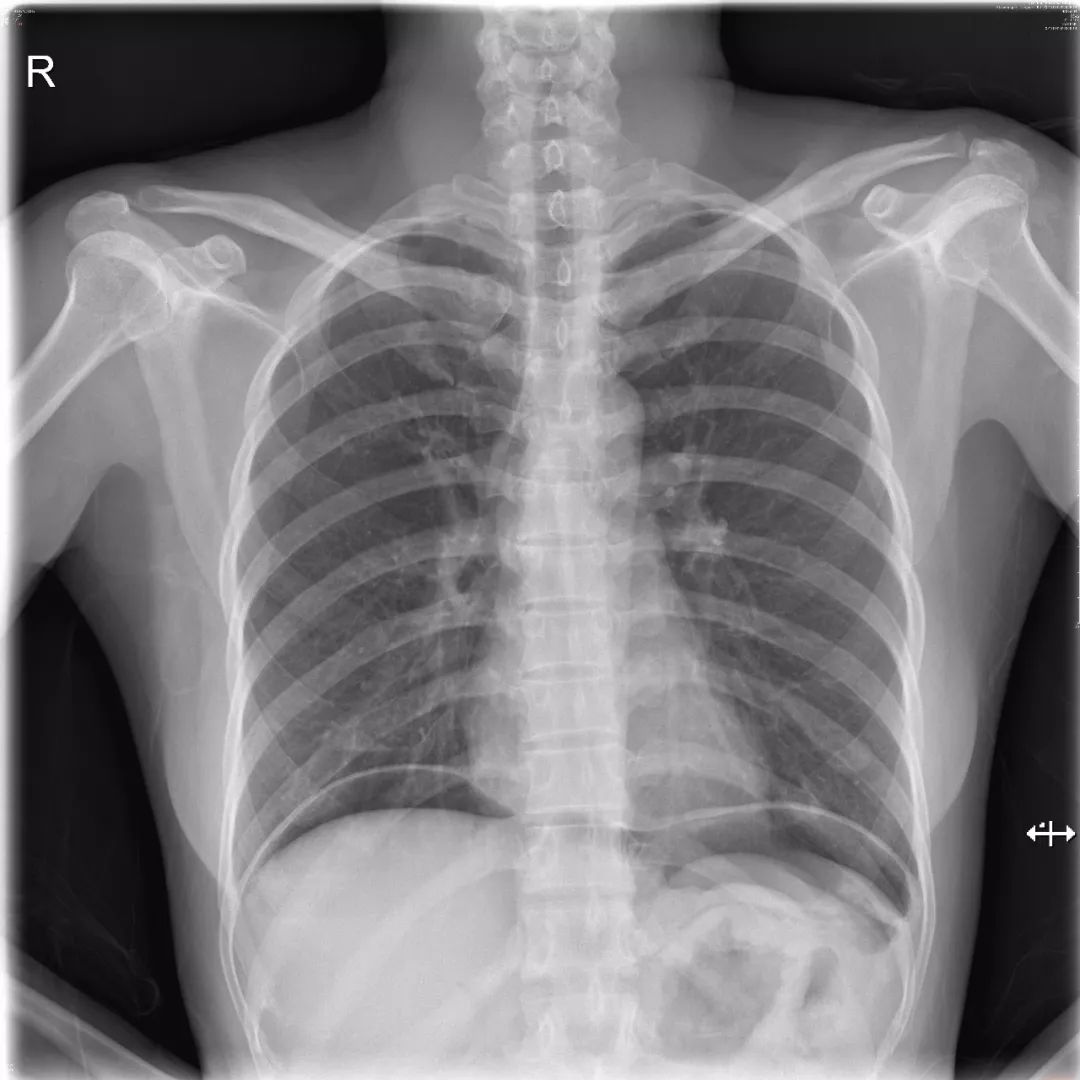

1) 气腹:气腹几乎均由消化道穿孔所致,最常见病因是胃及十二指肠溃疡穿孔。怀疑气腹首选立位胸片,右侧膈下更易观察,因为左侧膈下游离气体可与胃泡影重叠。发现膈下游离气体常能诊断为胃肠道穿孔,但不能定位。

气腹:立位胸片可见两侧膈下弧形透亮影,CT软组织窗及纵隔窗可见肝脏前缘气体密度影。